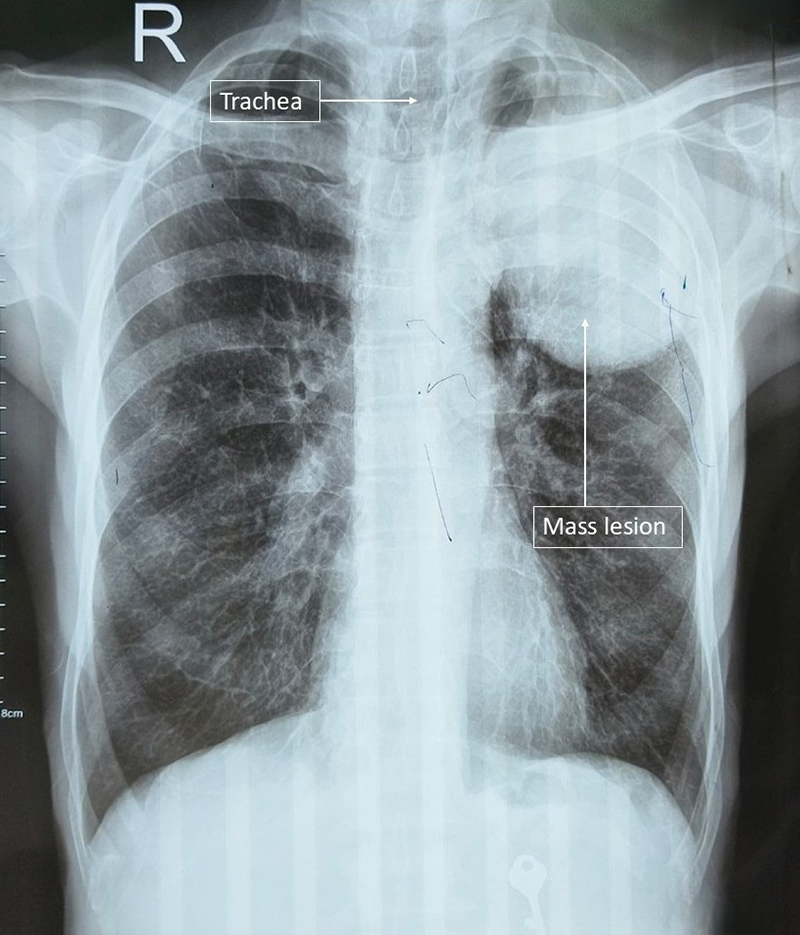

A 70-year-old man was referred to the Respiratory Medicine outpatient department of our institute by a private practitioner. On presentation, the patient complained of shortness of breath for 3 months and chest pain for last 1 month. The patient’s relatives reported his unintentional weight loss during the last year. His vitals were stable; on examination a dull percussion note was noted in left infra-scapular, axillary and infraclavicular area, breath sounds were absent, and no palpable cervical, axillary or inguinal lymph nodes were noted. A previous high resolution computed tomography (HRCT) thorax scan showed the presence of a large well circumscribed soft tissue mass lesion measuring 76 × 96 × 75 mm in the left upper lobe. Erosion of the 3rd and 4th rib with pathological fracture of the 3rd rib was also noted. Thin-walled emphysematous bullas were noted in the bilateral upper lobe. There was no evidence of lymphadenopathies. A chest x-ray with a posterior to anterior orientation view was done showing a mass lesion in left upper zone with bilateral hyperinflation changes (Figure 1).

Figure 1

Figure 1. Chest X-ray PA view showing lobulated mass lesion in left upper zone.